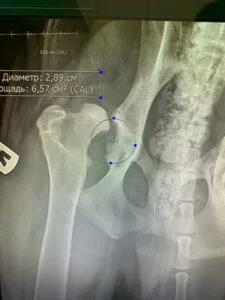

В 2021-2022 гг. — с соавторами разработал и запатентовал собственную систему для протезирования тазобедренного сустава V@Art (Виарт — https://v-art.info ). Данной системой пользуются ведущие врачи в России, а также в Белоруссии, Израиле, Кипре, Китае и Индии.

В октябре 2014 года сдал экзамене в Германии в GRSK на диагностику дисплазии тазобедренных суставов у собак. На сегодняшний день в России есть 2 практикующих специалиста, сдавшие экзамен на право диагностики дисплазии тазобедренных суставов, чьи заключения действительны в Европейских странах.

На 2020 год выполнил с коллегами больше всех в России операций по эндопротезированию тазобедренных суставов-операция, которая позволяет полностью восстановить опорную функцию тазовых конечностей у собак средних, больших и гигантских пород;